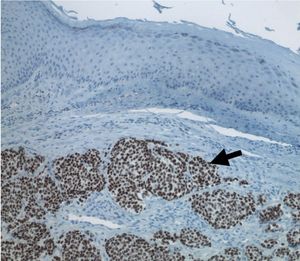

메르켈세포암종(MCC)의 진단은 피부 및 림프절의 임상 검사를 통해 의심스러운 부위를 결정하는 것으로 시작된다.[27] 확진을 위해서는 생검 조직을 검사하여 조직병리학적 특징을 확인해야 한다.[6][27] 이상적인 생검 표본은 펀치 생검이나 전체 두께의 피부 절개 생검으로, 전체 두께의 진피와 피하 조직을 포함한다. 현미경 검사에서 MCC는 신경내분비 특징(소금 후추 모양의 염색질, 희소 세포질, 활발한 유사 분열 활동)을 가진 기저 세포성 종양 둥지를 보인다.[6][27]

메르켈세포암종(MCC)의 진단은 피부 및 림프절의 임상 검사를 통해 의심스러운 부위를 결정하는 것으로 시작된다.[27] 확진을 위해서는 생검 조직을 검사하여 조직병리학적 특징을 확인해야 한다.[6][27] 이상적인 생검 표본은 펀치 생검이나 전체 두께의 피부 절개 생검으로, 전체 두께의 진피와 피하 조직을 포함한다. 현미경 검사에서 MCC는 신경내분비 특징(소금 후추 모양의 염색질, 희소 세포질, 활발한 유사 분열 활동)을 가진 기저 세포성 종양 둥지를 보인다.[6][27]면역조직화학(IHC)은 일반적으로 MCC를 소세포 폐암의 피부 전이, 흑색종의 소세포 변이체, 다양한 피부 백혈병/림프성 백혈병 및 유잉 육종과 같은 형태학적으로 유사한 다른 종양과 구별하는 데 필요하다. 시냅토피신 또는 크로모그라닌 A와 같은 신경내분비 분자 마커는 MCC 및 기타 신경내분비 종양의 특징이며, PAX5 또는 사이토케라틴 20과 같은 다른 마커는 이러한 종양과 MCC를 구별할 수 있다.[3][7] 종단 영상 검사도 전이성 소세포 폐암 진단을 배제하는 데 도움이 될 수 있다. MCC 진단이 내려지면, 감시 림프절 생검 및 영상 검사가 예후와 후속 치료 옵션을 결정하는 병기 결정 과정의 일부로 권장된다.[6][27] 영상 검사에는 양전자 방출 단층 촬영술 또는 CT 스캔이 포함될 수 있다.[28]